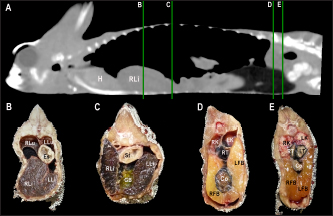

Fig. 4. Sagittal precontrast CT image displayed in soft tissue window (A) and transverse cross-sectional views of gross anatomical sections at the level of the liver (B), gallbladder (C), fat bodies (D), and kidneys (E) in a veiled chameleon (C. calyptratus). The right of the patient is on the left of the image. H, heart; RLu, right lung; LLu, left lung; Es, Esophagus; RLi, right liver lobe; LLi, left liver lobe; ST, stomach; GB, gallbladder; RK, right kidney; LK, left kidney; RT, right testicle; LT, left testicle; RFB, right fat body; LFB, left fat body; Co, colon.

Heart, liver, including caudal vena cava (CVC), hepatic vessels, and gallbladder, esophagus, stomach, intestines, cloaca, gonads, fat bodies, kidneys, and when distended, urinary bladder were identified in the CT images with the aid of the anatomical sections (Fig. 4). The spleen, pancreas, and adrenal glands could not be identified. Measurement values of the liver, testes, fat bodies, and kidneys observed in CT in veiled and panther chameleons are seen in Table 1.